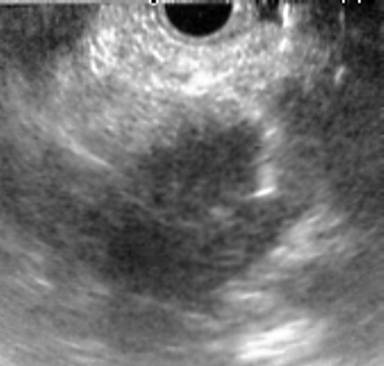

EUS (Olympus KeyMed, Southend, United Kingdom) demonstrated that the mass was extraluminal, peripancreatic and most likely to represent a metastasis in a local lymph node. EUS-FNA was therefore performed by means of trans-neoduodenal puncture (Figure 3) with a 22-gauge needle (Cook Medical, Limerick, Ireland). Histopathological examination of the biopsy specimen confirmed invasive malignancy. The multidisciplinary team consensus was to perform CT staging and offer a pylorus-preserving pancreaticoduodenectomy in the form of pylorus-preserving Kausch-Whipple pancreaticoduodenectomy.

Figure 3. EUS-FNA of the 2 cm hypoechoic mass with a 22-gauge needle clearly seen within the lesion. This confirmed adenocarcinoma. |